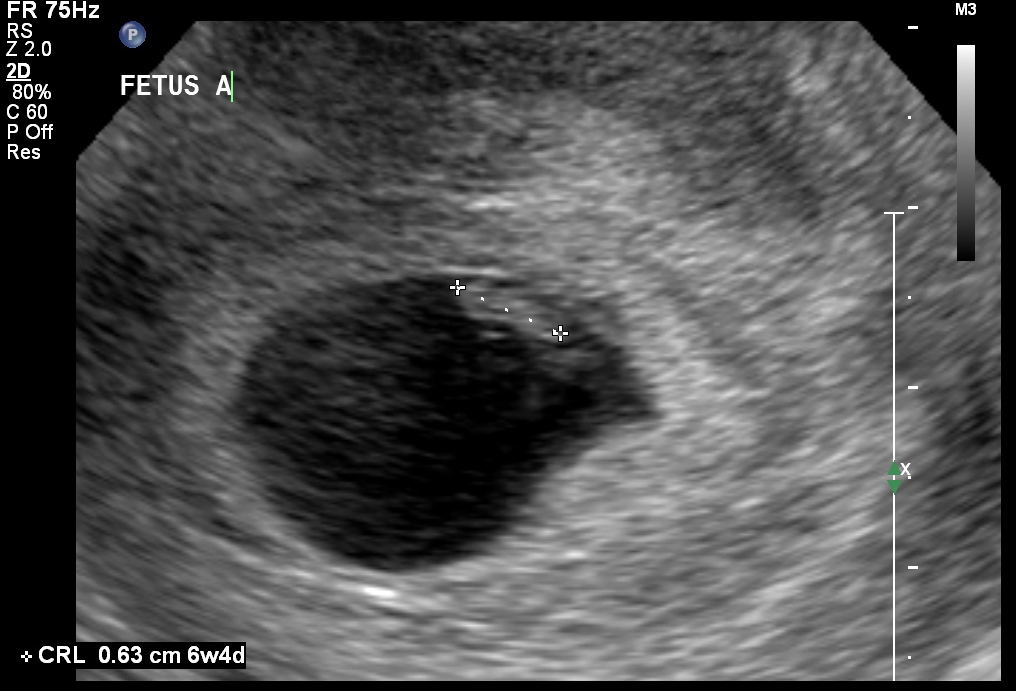

Everything looked good.  We got to see the heartbeats, but they were too small to hear.

imageimage

• We didn't know. It had crossed my mind, but I thought for sure it wouldn't be twins because they don't run in our family. H about freaked out when she said there were 2 sacs. @mmnumber5‌ I didn't know that.

• I'm also in shock. I was just getting used to the idea of being pregnant, now I have to get used to the idea of twins. I was extremely nervous about this u/s because my gut was saying twins, but I didn't want to believe it. I think he almost started crying when he found out it was twins. I think he was happy to step out of the room for a few minutes when Alexis started to get fussy. Finding out we are having twins has thrown off our announcement plans. We had planned a cute way to announce, but when we found out it was twins we had to tell our families right away.